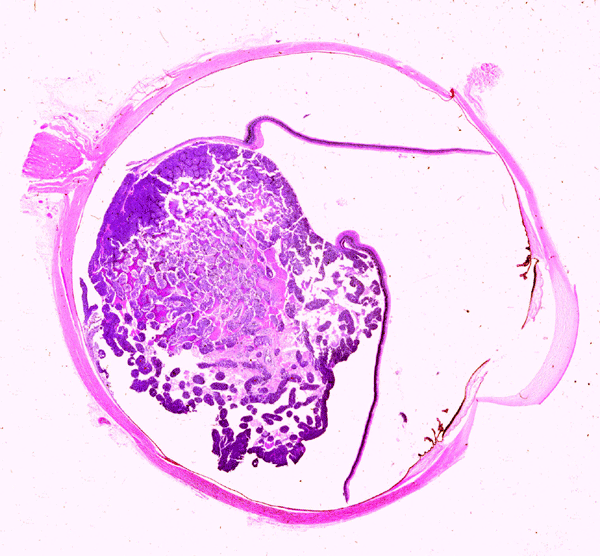

Clinical information The patient was a 2 year-old girl. She was brought to the doctor because her mother found that her left eye looked "funny". On ophthalmic examination, the pupil of the left eye did not response to light and also has a white reflection. Fundic examination disclosed a retinal tumor. The globe was enucleated. Representative photographs are taken from the surgical specimen.

A. B. C. D.

On the whole mount of the globe, there is an exophytic neoplasm that occupies about one-third the volume of the vitreous. The surface of the retina is free of tumor deposition (Panel A). The retina is detached by the mass. There are some pink, necrotic material at the core of the tumor (Panel B). On medium and high-magnification, the tumor is composed of densely packed small cells with hyperchromatic nuclei  without prominent nucleoli. A large number of the cells arrange in rossettes with a well-defined luminal border (Flexner-Wintersteiner rossettes) (Panel C and D). The tumor is confined within the globe and the optic nerve is free from invasion.